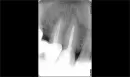

Откололся кусочек эмали, пошел к стоматологу, он сказал, что в зубе кариес, нужно вынимать какой-то инструмент, лечить корень, пломбировать и ставить коронку. Также доктор сказал, что на снимке (в конце корня) что-то страшное черное и его нужно срочно лечить. Также направил снимок своему доктору (т.к. нахожусь сейчас в другом городе и не имею возможности его посетить), он мне сказал, что не видит на снимке ничего страшного и его нужно просто запломбировать и поставить коронку.

Подскажите, пожалуйста, есть ли на снимке что-то страшное и какое должно быть последующее лечение? Зуб тринадцатый, не болит и не беспокоит, коронка не стоит.

На обоих запломбированных зубах имеется хронический процесс (периодонтит), причина - некачественное лечение каналов. Если лечение, это дело рук вашего доктора, тогда понятно его неграмотное отношение. Оба зуба и тринадцатый, и четырнадцатый под коронкой, необходимо перелечить.